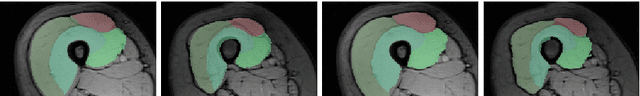

Abstract:The Random Walks (RW) algorithm is one of the most e - cient and easy-to-use probabilistic segmentation methods. By combining contrast terms with prior terms, it provides accurate segmentations of medical images in a fully automated manner. However, one of the main drawbacks of using the RW algorithm is that its parameters have to be hand-tuned. we propose a novel discriminative learning framework that estimates the parameters using a training dataset. The main challenge we face is that the training samples are not fully supervised. Speci cally, they provide a hard segmentation of the images, instead of a proba- bilistic segmentation. We overcome this challenge by treating the opti- mal probabilistic segmentation that is compatible with the given hard segmentation as a latent variable. This allows us to employ the latent support vector machine formulation for parameter estimation. We show that our approach signi cantly outperforms the baseline methods on a challenging dataset consisting of real clinical 3D MRI volumes of skeletal muscles.